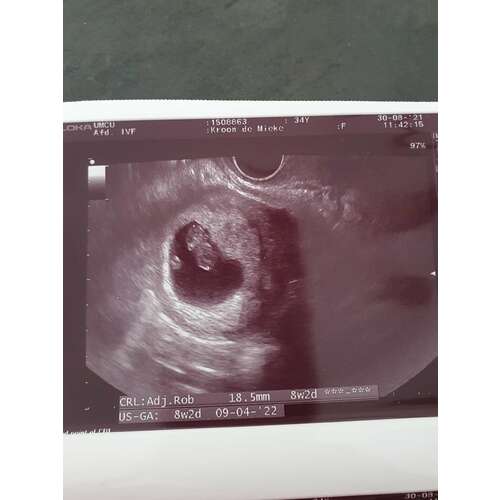

Echo van vandaag 8+2